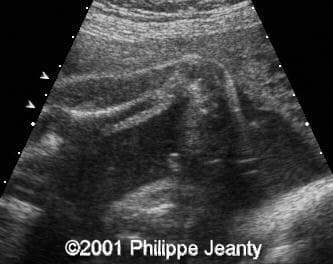

This fetus has a small amount of bowing and shortening of the right leg (compare to the left leg on the second image):

image19

image20